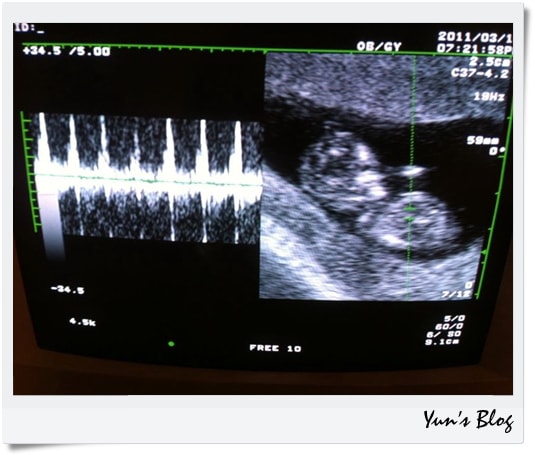

♥100.02.17 小兔子有了心跳

終於盼到了第一次產檢了,

帶著忐忑不安的心情躺在檢查台,讓冰冰涼涼的超音波儀器滑過我的肚皮,

我不敢問任何的問題,也不敢看電腦螢幕,

直到超音波師告訴我:很好!胚胎有1.8公分囉!

我這才把頭慢慢移向螢幕。

哇!小碗豆真的長大咧!

現在看起來像是…香菇?

然後這朵香菇,居然還會有心跳?

噗通!噗通!噗通!像是打鼓一樣、強而有力,

這個聲音彷彿在告訴我:媽咪!安啦!我很健康,妳不要擔心。

原來,喜極而泣,就是這麼一回事。

♥100.03.08 小兔子有了頭跟身體

於是我就近找了一間婦產科診所看診,順便照了超音波,

沒想到距離上次2月17日產檢還不到1個月的時間,

小香菇已經變成一個人了!

怎麼會這麼好玩啊!

才幾天不見,他(她)就悄悄長成人的形狀了。

看到了嗎?

照片的下方是頭、上方是身體,小兔子呈現倒栽蔥的姿勢,

醫生說這時候開始,就可以正式稱他(她)為胎兒囉!

♥100.03.10 小兔子會敬禮

懷孕來到第10週,進行了我第一次的正式產檢,

說也神奇!

當超音波師幫我檢查到一半,

已經有6公分大的小兔子居然舉起了手呈現敬禮狀,

有看到嗎?照片上方彎曲的那一條就是手,

他(她)似乎知道今天還有外婆在,想要討她歡心。

過了一會兒,寶寶翻身了,剛好呈現平躺狀,

這是我第一次看到寶寶的側身,而且彷彿看到了眼睛鼻子,

他(她)在我肚子裡,會翻滾、會拳打腳踢,一整個是很忙碌的狀態呢!

♥100.03.22 早期妊娠風險評估

因為是屬於特殊檢查,過程會比一般產檢時照超音波仔細許多,

頭圍、身長、手指頭、腳趾頭、心臟血流情況,通通都會照得一清二楚,

醫生也會從寶寶的透明頸間帶厚度,判斷是否為唐氏症高風險兒。